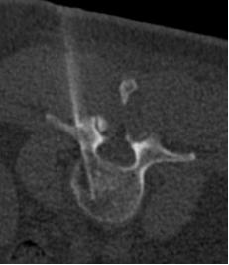

联合骨组织/软组织活检

|

椎体破坏 |

局麻 |

14G骨入路 |

16G TruCut 活检针:Osteolytic bone metastasis from urothel carcinoma |